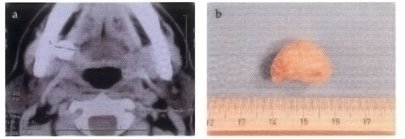

Fig.2 a) Calcolo entro il dotto escretore della ghiandola sottomandibolare destra. TC in assiale. h) Il calcolo asportato.

(vedi Fig.2).